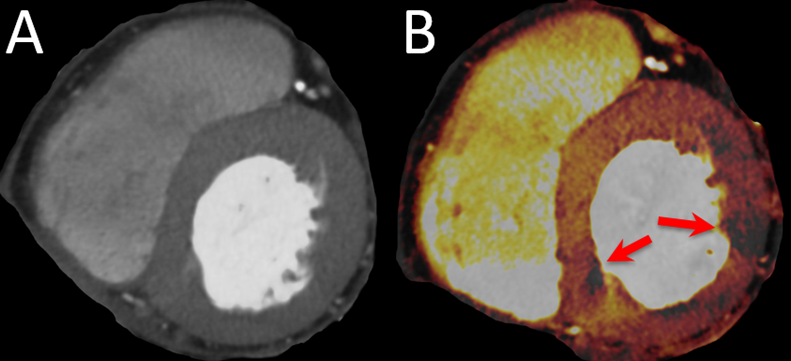

Another example of cCTA exceeding the limits of pure anatomical testing for CAD is CT perfusion (CTP). The anatomical visualization of coronary arteries by cCTA is followed by vasodilator stress and repeated CT imaging to assess perfusion deficits in patients where cCTA alone was not able to exclude hemodynamically relevant stenosis [61]. CTP may also be performed without vasodilator stress, although the diagnostic value is limited [62].CTP has been shown to possess incremental diagnostic value over cCTA alone and was comparable to PET-CT or vasodilator stress CMR with respect to invasive FFR as reference [61,63–67]. An example is given in Figure 4. Limitations include the increased radiation exposure, longer and unpredictable scanning times since CTP only is used when the on-site imaging specialist is not able to exclude hemodynamically relevant stenosis on the first images, and the current lack of large multi-center and multi-vendor studies [61].

Figure 4. Imaging example of a CTP. A 78-year-old female patient with atypical angina and intermediate pretest probability. (A) shows the multiplanar reconstructions of the basal short axis with a DECT at 90 kV and 150 kV. (B) shows the perfused blood volume which is reduced in two segments (red arrows).